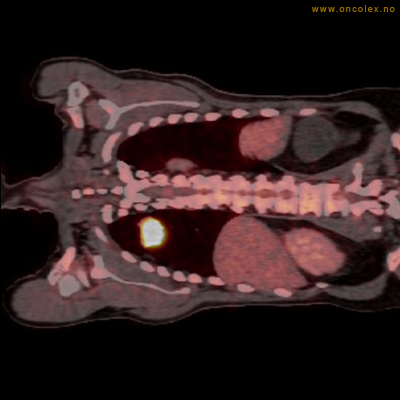

PET/CT (PET: Positron Emisjons Tomografi/ CT: Computer Tomografi) er en avansert nukleærmedisinsk bildetakingsmetode. Metoden er et godt dokumentert, veletablert og svært nyttig verktøy i bildediagnostikk ved kreft. Et PET-kamera gir tredimensjonale bilder av hele kroppen. Integrert CT gjør at informasjonen fra PET blir lokalisert anatomisk nøyaktig.

Kort beskrivelse av undersøkelsen

Gjennom en nål (plastkanyle) i en blodåre i armen vil du få et radioaktivt stoff. Det mest vanlige er radioaktivt druesukker (18F-FDG). Stråling fra det radioaktive stoffet registreres i PET-skanneren og viser hvordan dette stoffet fordeler seg i kroppen. Det normale opptaket av det radioaktive stoffet vil være endret ved sykdomsprosesser. Celler med høyt stoffskite, som for eksempel kreftceller, har økt opptak av sukker. Ved undersøkelsen kan man dermed ofte se større opptak av det radioaktive sporstoffet i kreftsvulster.  Siden CT tas samtidig, kan PET og CT bildene legges sammen og vise nøyaktig hvor i kroppen det økte opptaket er.

Eksempler på funn

Vev som tar opp mer radioaktivt stoff, synes som hvite områder som lyser opp mer i forhold til annet vev som tar opp mindre sukker.